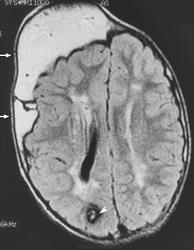

Клинические проявления заболевания характеризуются выраженным полиморфизмом. Наряду с типичной симптоматикой - парциальным гигантизмом рук и ног, гемигипертрофией, артериовенозными аномалиями, макроцефалией - наблюдаются разнообразные опухоли: бородавчатый эпидермальный невус, гемангиомы, лимфангиомы, липомы, гамартомы. Иногда отмечаются косоглазие, экзофтальм, миопия, прогения, варикозное расширение вен, разрастание кожи на подошвах. Примерно в 55% случаев выявляется умственная отсталость, в 13% - судорожный синдром. Наблюдались также больные с изолированной макродактилией, спленомегалией, избирательной патологией глаз и черепа в виде множественных менингиом, полимикрогирии, ретинальной пигментной дегенерации и атрофии зрительного нерва. Продолжительность жизни пробандов, как правило, невелика и колеблется от 3 до 40 лет. Смерть наступает чаще от злокачественных новообразований. Описаны такие опасные для жизни осложнения, как венозные тромбозы и эмболия легочной артерии. Так, A. Stavotinek и соавт. в 2000 г. сообщили о 3 больных, умерших в возрасте 12, 17 и 25 лет от эмболии легочной артерии [9].